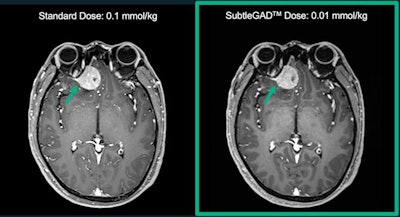

SubtleGAD uses AI to reduce necessary gadolinium dose during MR exams, and it can process images at 10% of typical doses, the company said. It is part of the company's portfolio of AI tools for radiology, which also includes SubtleMR and SubtlePET.

MRI images processed with Subtle's SubtleGAD algorithm at 10% of the original gadolinium dose. Image courtesy of Subtle Medical.SBIR is a U.S. government program coordinated by the Small Business Administration.